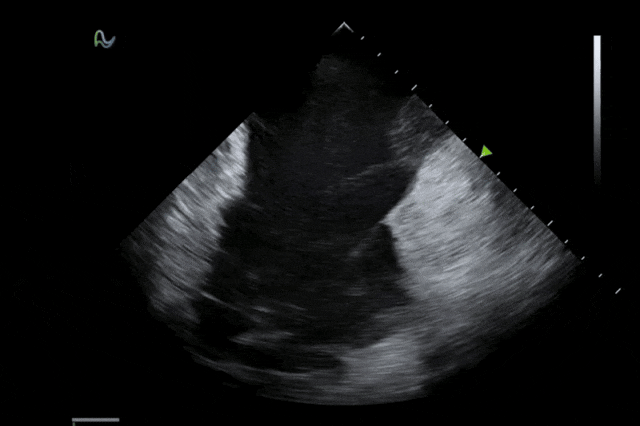

心腔内超声(ICE)被誉为心脏介入手术的"黄金眼",能够通过微创方式实时呈现心脏内部结构和血流成像,为房颤消融、左心耳封堵、先心病介入等手术提供精准成像导航。相较于传统影像手段,ICE具有无辐射、实时成像、操作灵活等显著优势,已成为国际指南推荐的核心诊断技术。

本次获批的ICE导管在全球首次采用了80阵元大孔径高密度探头设计,较传统普通的64阵元产品大幅度提升了成像分辨率、成像深度和图像对比度,可清晰辨识心脏细微结构和血流,为复杂手术提供更可靠的超声成像支持。同时,8F导管凭借更小的外径,显著提升导管通过性和操控性,对病人创伤更小,尤其适合血管条件受限或小心脏患者;10F导管则凭借其优质的成像质量,为复杂心脏介入手术提供精准的影像引导。